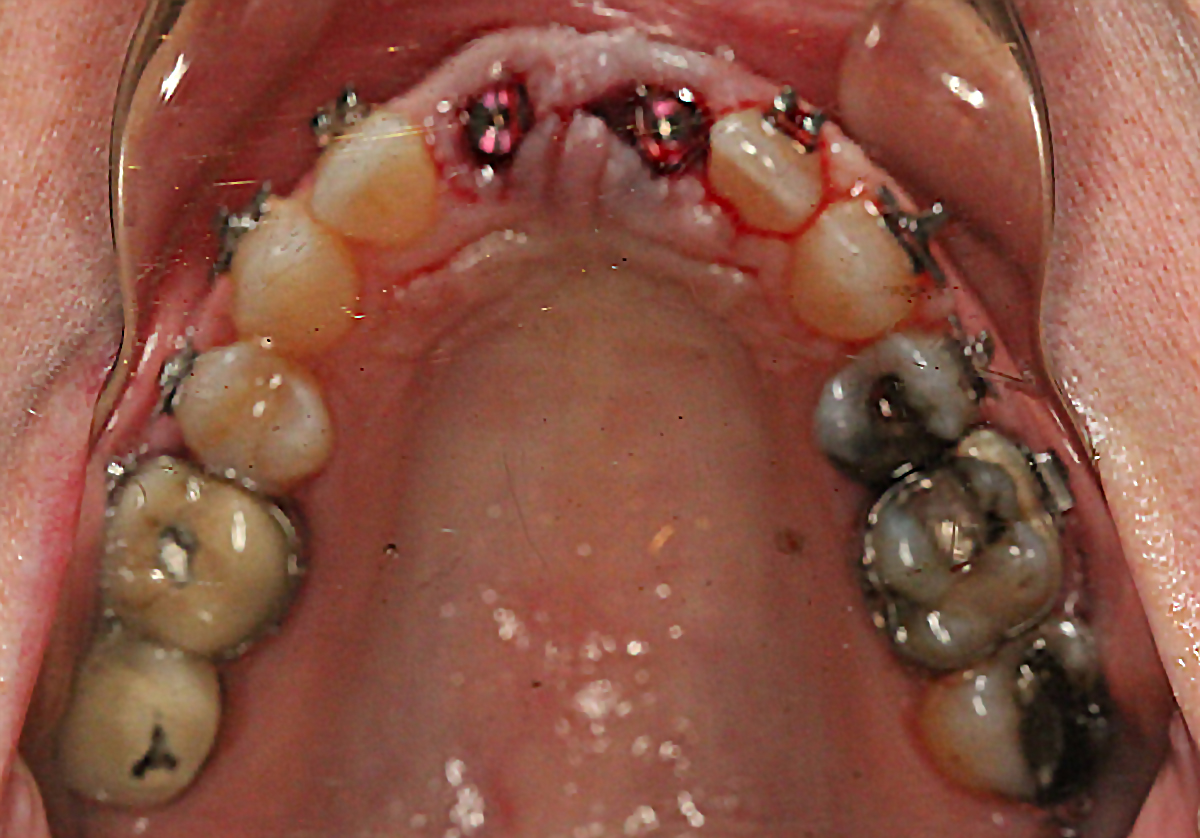

Extraction after forced eruption can allow for a much more favorable implant site compared with extraction alone. This is possible because the tension applied to the periodontal ligament during orthodontic tooth movement stimulates osteoblastic activity to induce new bone formation. As the tooth moves coronally during extrusion, soft tissue and bone attached to the periodontal fibers migrate in the same direction. As a result, forced eruption can be used to enhance the quality and quantity of both hard and soft tissue of future implant sites.

The special report presented below illustrates how orthodontic extrusion was successfully used to improve the periodontal architecture prior to the placement of two adjacent implants in the esthetic zone and thus allowed for a more ideal restorative result.